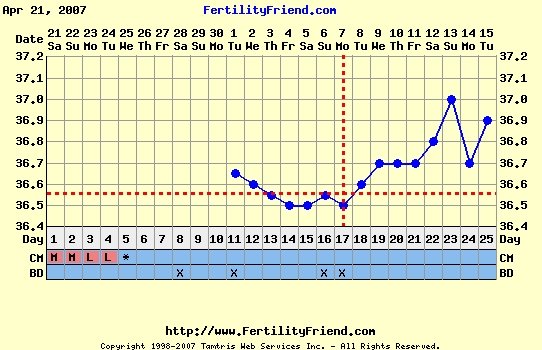

Bettike, tök jó végre tőled egy ilyen szép görbét látni a hiperciklusaid után!

És nagyon simogattyajakicsiszivemet, hogy az én babás görbém ilyen példaértékű. Úgyhogy Bonikám, tiád a pálya, úgyis utálom, hogy mindig az én hsz-om az utolsó a másik hőmérősben.